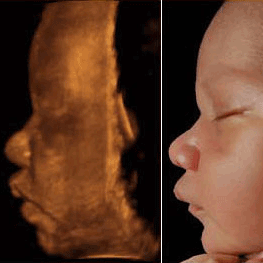

Ultrasound Diagnostic Center specializing in 3/4D. Office:Lehigh Acres,Fl. Mobile services offered throughout Florida. 239-849-9341. http://Miraclesimaging.com